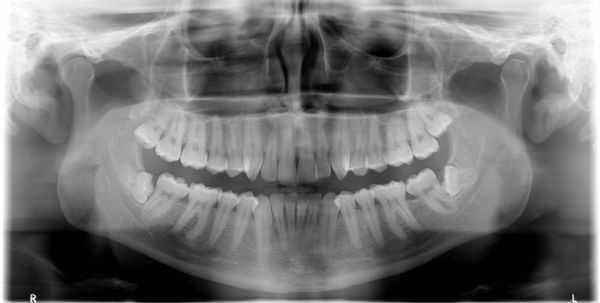

(Слева) На панорамной рентгенограмме у пациента с двухлоронним передним вывихом визуализируется правый мыщелок, смещенный кпереди и кверху относительно сулавного возвышения. Обратите внимание на явный передний открытый прикус, в то время как моляры находятся в окклюзии.

(Справа) На панорамной рентгенограмме у этого же пациента определяются аналогичные изменения слева. Открытый прикус обусловлен неправильным передним положением мыщелка, контакт задних зубов - его верхним положением.

2. Рентгенография при вывихе височно-нижнечелюстного сустава (ВНЧС):

• Радиографические признаки:

о Передне-верхнее положение мыщелков по отношению к суставному возвышению

о Панорамная рентгенография для первоначальной оценки

(Слева) На рентгенограмме в боковой проекции у этого же пациента определяется прогнатическое положение нижней челюсти и открытый передний прикус вследлвие передне-верхнего смещения мыщелков нижней челюсти.